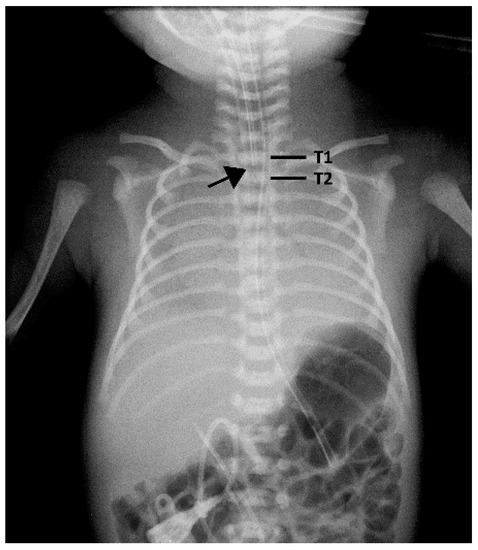

2.2. Depth of Endotracheal Tube